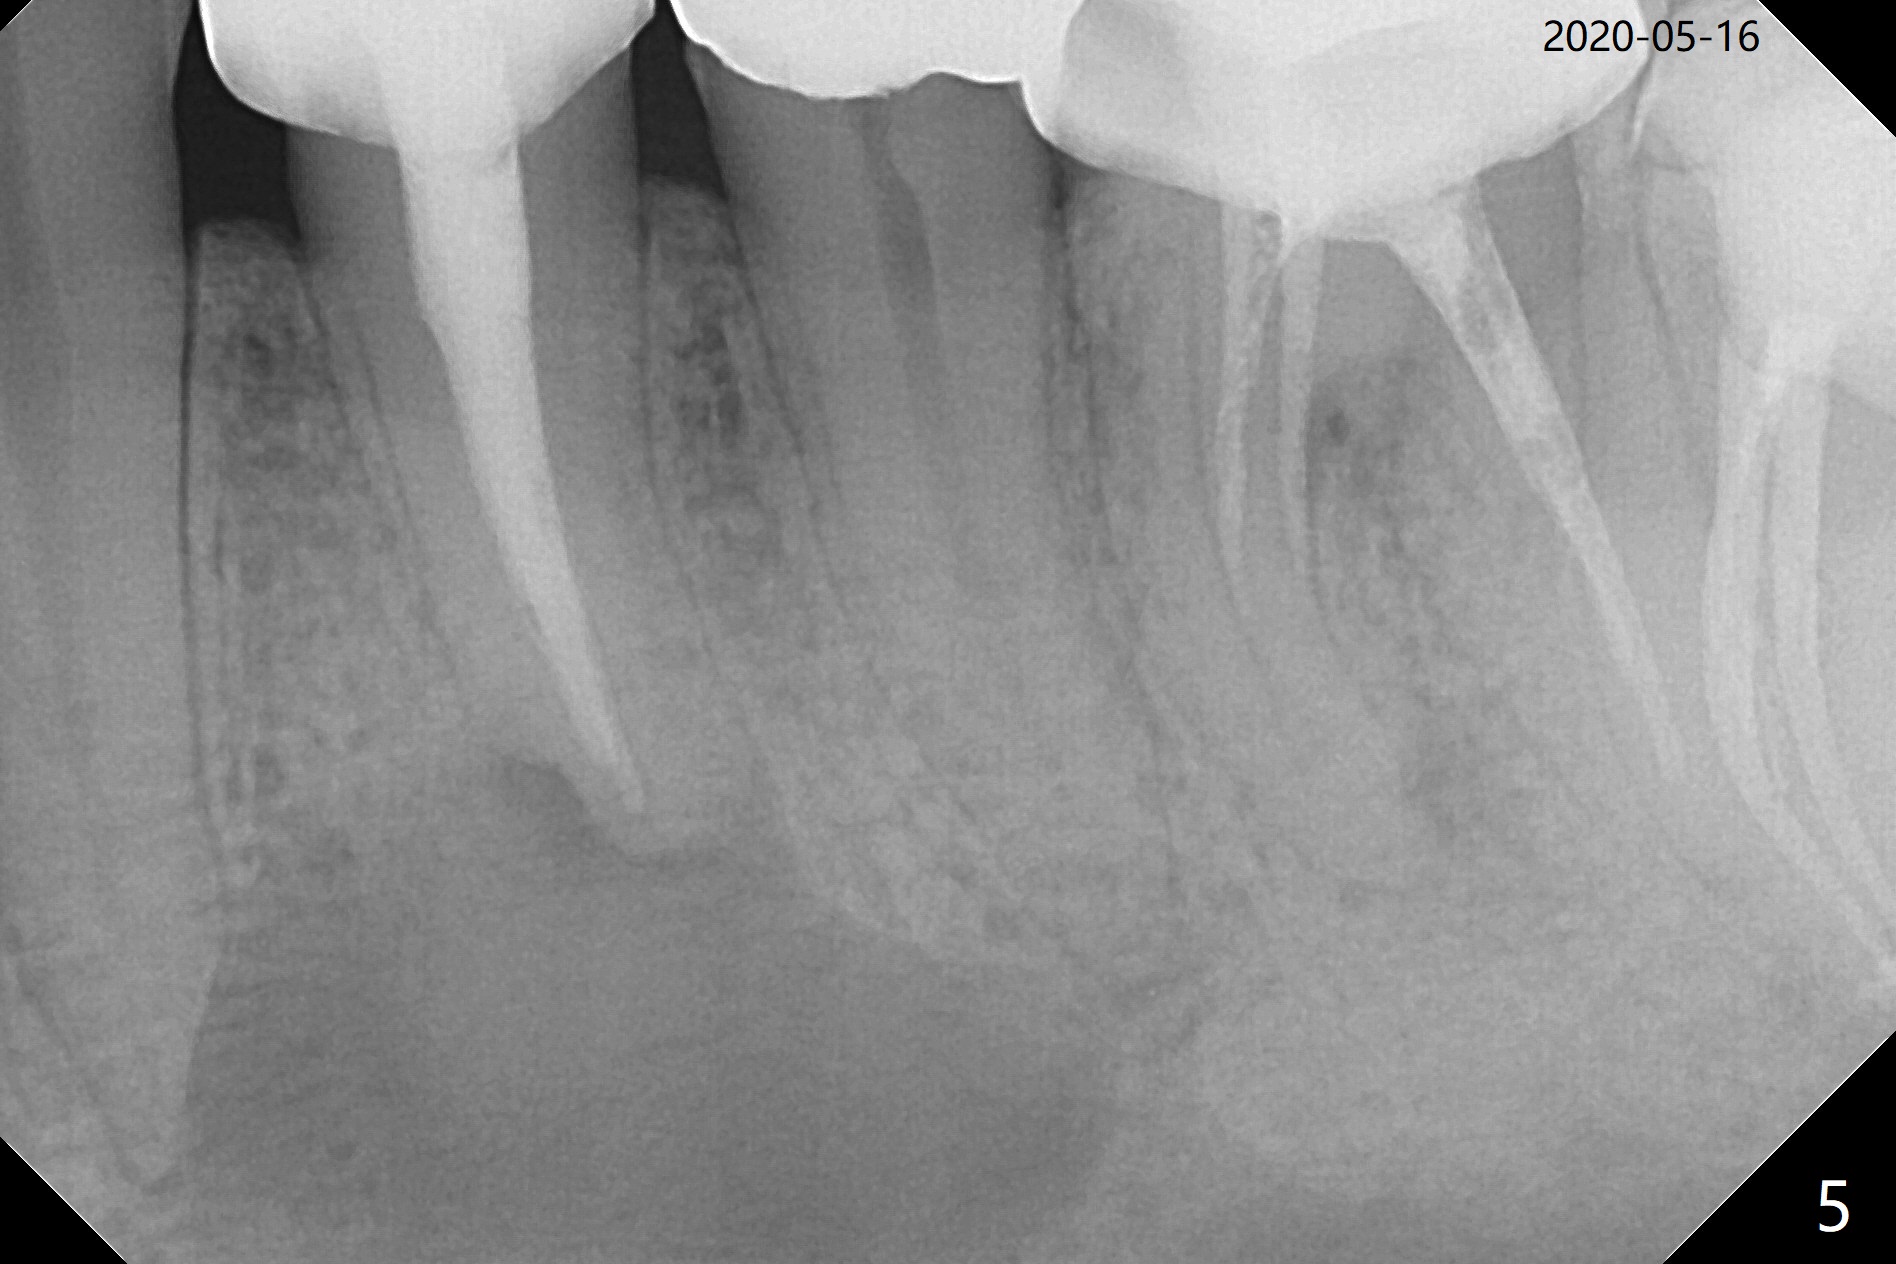

A 37-year-old man complains of food impaction between #14 and 15, which may be related to mesioangular impaction of #16 (Fig.1 ^ (* a supernumerary premolar; #20 asymptomatic after RCT retreatment)). When the third tooth is removed, it is smaller than expected. Intraop X-ray reveals a normal sized 3rd molar in situ (Fig.2 ^). Therefore the microdontia removed is a supernumerary tooth. The tooth #16 is then extracted. The diastema appears to persist 2 years 7 months postop (Fig.3), although gingival swelling and pain reduces. There is a significant increase in PARL at #20, supported by 2 PAs (Fig.4,5). The tooth has no mobility with normal periodontal pockets. There is no paresthesia of the lower left lip.